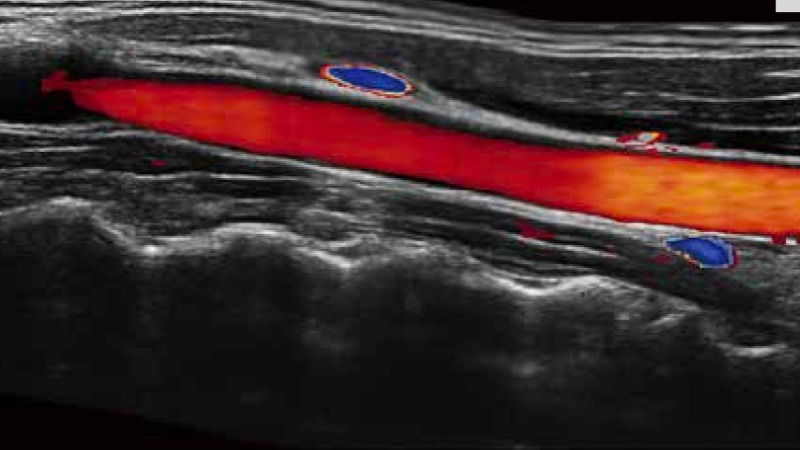

SR Flow高分辨率血流成像

高分辨率血流成像技术提高了对低速血流信号的检测能力。在提高空间分辨率的同时,也克服了血流外溢现象,为用户提供更加真实的血流动力学信息。

实时宽景成像技术

通过彩色血流和实时宽景相结合,可观察到完整的动静脉血流,方便医生检查。实时扫查过程中,如有任何操作失误也可以很容易地进行回扫擦除,而不会中断扫查。